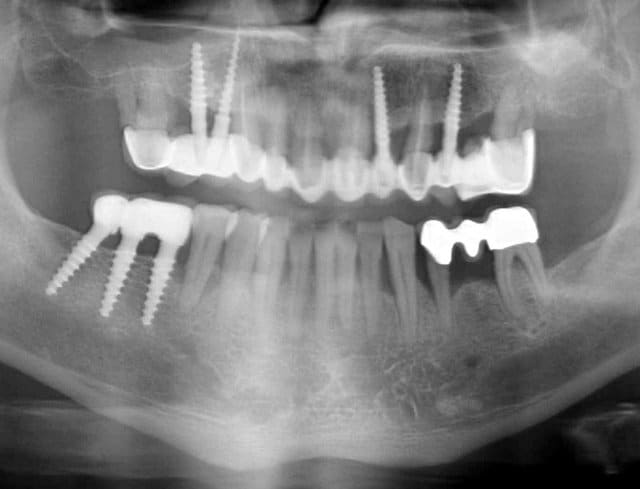

Bonjour flicflac je suis désolé de ma réponse tardive, oui il est vrai que ce n est pas beaucoup documenté ... je serai un menteur de dire que que je n ai jamais perdu des implants, surtout entre la 2eme et 8eme semaine après l implantation.Un échec vraiment à cause de la perte osseuse et avec le même process cela est arrivé une fois avec une madame, où l´os était encore infecté ( avant la chirurgie),mais après l ´échec (c était à la position 35) on a pu laisser le bridge. Malheureusement je n ai pas toutes les photos ici à Mallorque sur mon PC portable. Ci dessous une photo après 10 ans 46 47 et les implants au maxillaire.

Oui ca semble ....sur la opg radio tu peux voir la situation seulement deux semaines après l´implantation immédiate 34 jusqu´à 36 et 45, les derniers 2 photos montrent la même situation après un an ( où on a enlevé la supra construction pour un contrôle). Sur ce cas je voulais montrer la bonne régénération osseuse et de la gencive.

23 opg komplett ypnjdh - Eugenol